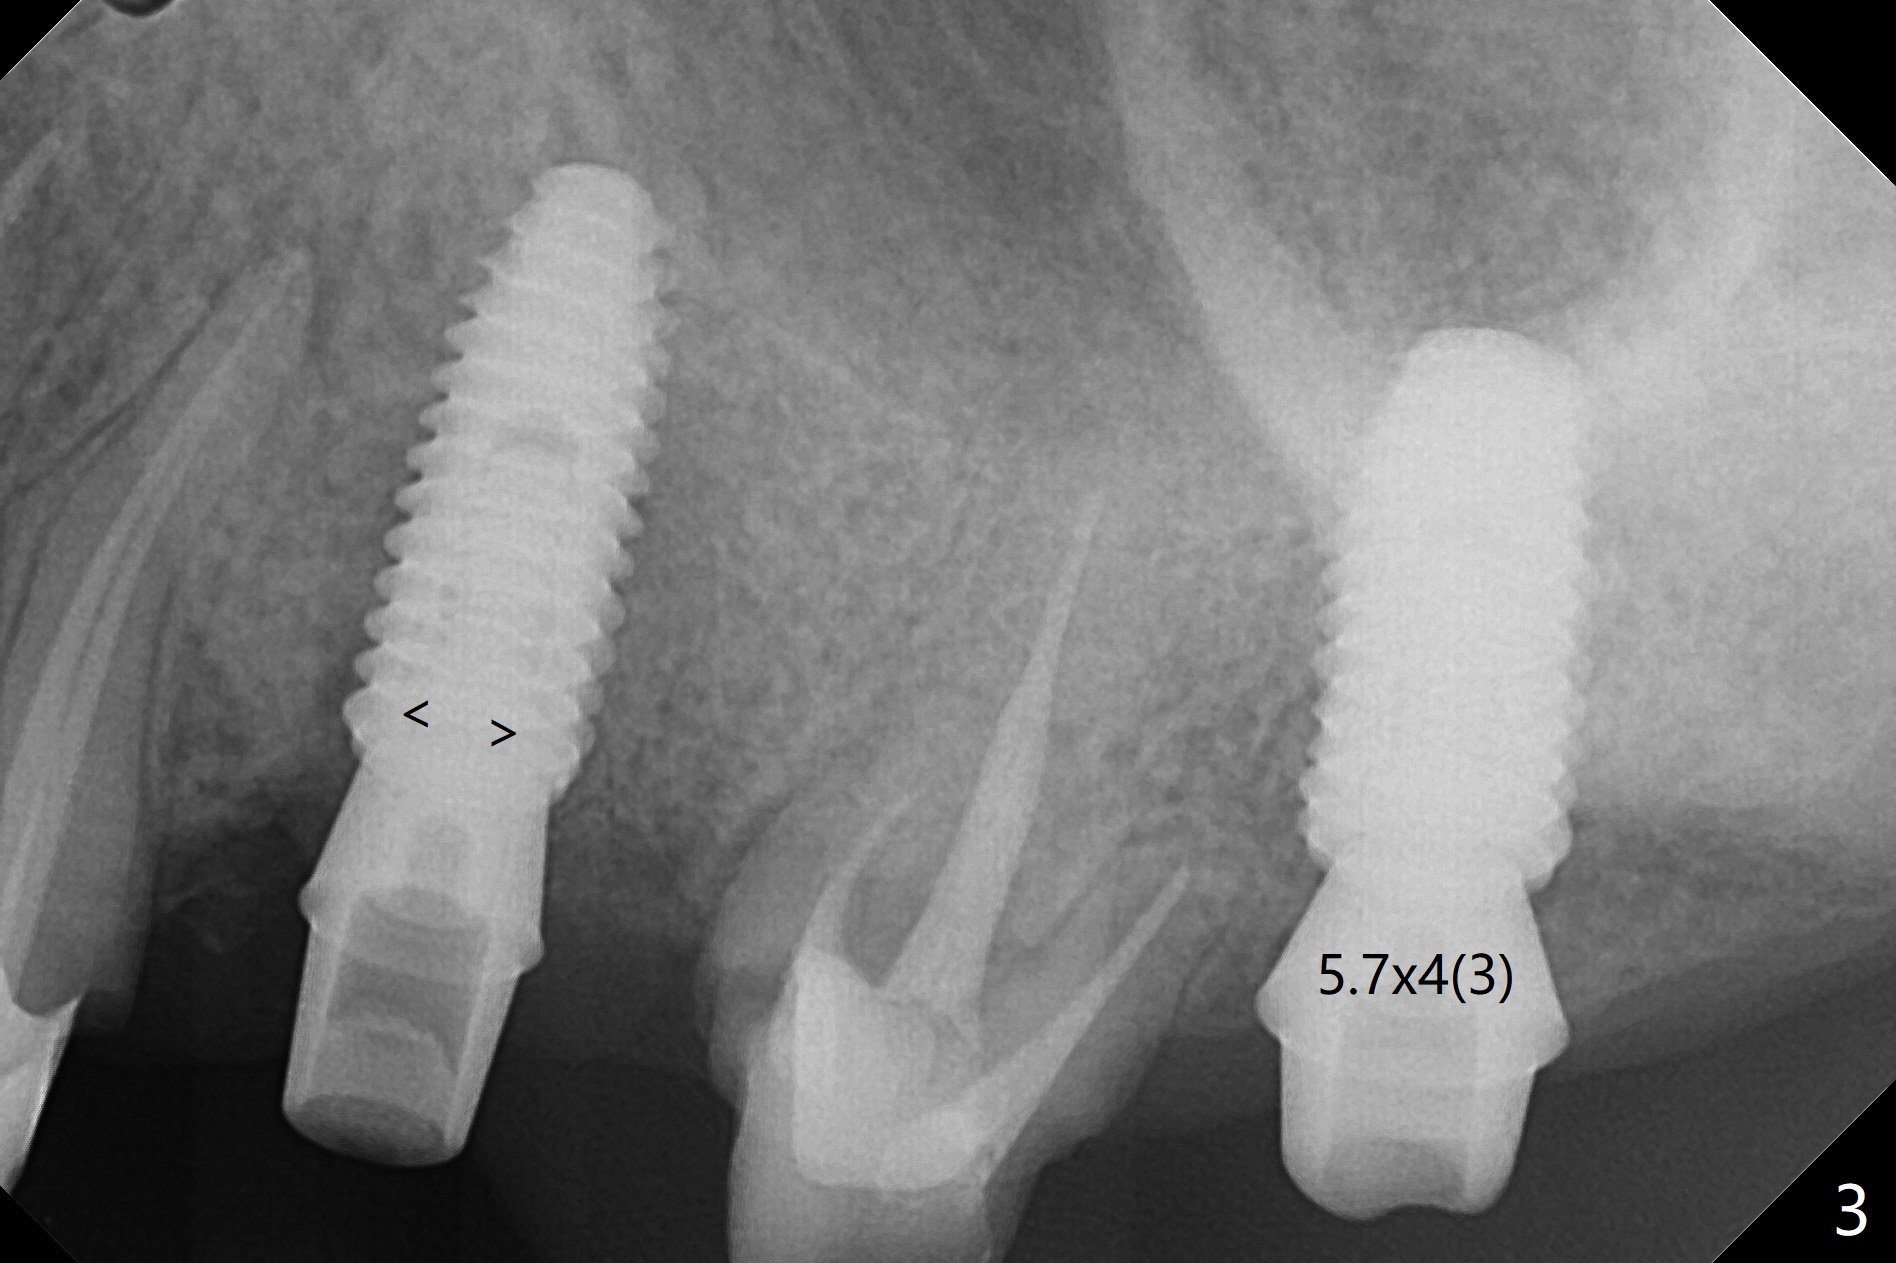

After underdrilling (3.5x14.5 mm drill (10.5 mm offset), a 4.5x11.5 mm implant is unable to enter the osteotomy at #13; following use of 4x10 mm drill (partial normal drilling), the implant is inserted smoothly with insertion torque ~ 35 Ncm. Sticky bone is placed in the bony portion of the buccal gap, while 2 pieces of PRF membrane in the gingival portion of the buccal gap. The bone density at #15 is low, the insertion torque is ~15 Ncm with normal drilling without cortical tap (Fig.1). The procedure is smooth in part due to no sinus involvement (red dashed line). An immediate provisional FPD is fabricated for #12-14. But local oral hygiene is difficult to maintenance. When the wound heals at #13, the FPD is removed. The bone loss is minimal nearly 4 months postop; the abutment at #13 is incompletely seated (Fig.2 arrowheads: gap). After repositioning, the abutment is re-seated completely without gap (arrowheads); a 5.7x4(3) mm cemented abutment is placed at #15 (Fig.3,4). Four crowns are cemented 4 months 10 days postop (Fig.5).

Upper Premolar Molar Immediate Implant, Trajectory Xin Wei, DDS, PhD, MS 1st edition 06/20/2019, last revision 11/02/2019